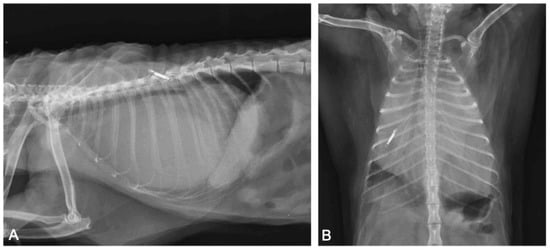

Figure 5. Transverse (A) and sagittal (B) TC sections of the thorax. Severe pericardial effusion (asterisks) with mild right dorsal-lateral heart (H) displacement.